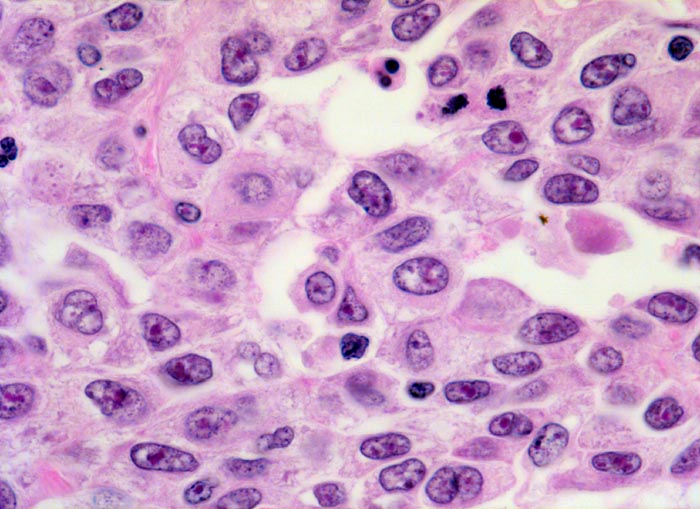

• Fragmente eines papillär aufgebauten Karzinoms.

• Tumorzellkerne mit ausgeprägter Pleomorphie und Hyperchromasie sowie prominenten Nukleolen. Fehlende polare Ausrichtung der Tumorzellen. Zahlreiche Mitosen und Apoptosen.

• Kleinherdige Tumornekrosen.

• Invasion der Lamina propria (Tumorfragmente links): Kleine Tumorzellgruppen oder Einzelzellen haben die Basalmembran an wenigen Stellen durchbrochen und liegen in der Lamina propria.